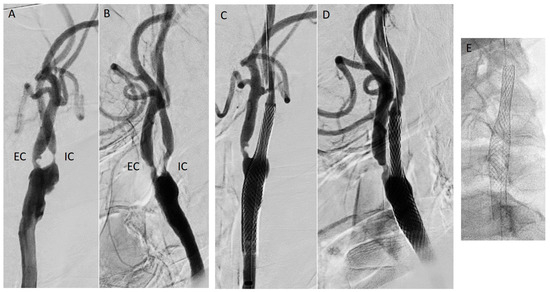

Carotid Restenosis: Incidence, Pathophysiology and Therapeutic Options

Restenosis after carotid endarterectomy and carotid artery stenting remains the main complication after both surgical and endovascular treatment of carotid stenosis, with a 2-year restenosis rate of 6–12%. Complex inflammation processes are the cause of early (<2 years) and late (>2 years) restenosis [...] Read more.

Restenosis after carotid endarterectomy and carotid artery stenting remains the main complication after both surgical and endovascular treatment of carotid stenosis, with a 2-year restenosis rate of 6–12%. Complex inflammation processes are the cause of early (<2 years) and late (>2 years) restenosis and principal systemic risk factors are female gender, hypertension, diabetes, dyslipidemia, and smoking. Non-procedural treatment includes lifestyle modifications and best medical therapy. The procedural treatment, considered mostly for symptomatic patients, includes different open and endovascular techniques. The management should be personalized according to patient and plaque characteristics. Full article

Graphical abstract